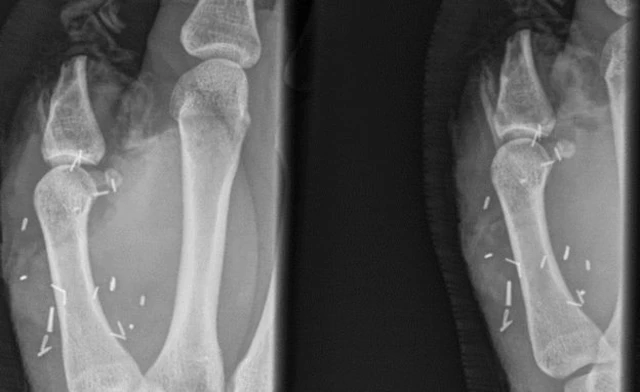

ऑस्ट्रेलिया के एक पशुपालक के पैर के अंगूठे को हाथ के अंगूठे की जगह पर ट्रांसप्लांट किया गया है.

20 साल के ज़ैक मिशेल जब खेत में काम कर रहे थे, तब एक बैल ने उनके अंगूठे को बुरी तरह कुचल दिया था.

मिशेल के मौजूदा ऑपरेशन से पहले दो बार डॉक्टरों ने उनके हाथ के कुचले हुए अंगूठे को ही फिर से जोड़ने की कोशिश की लेकिन वो कामयाब नहीं हो पाए.

पैर का अंगूठा हाथ में लगाने के लिए आठ घंटे का लंबा ऑपरेशन करना पड़ा.